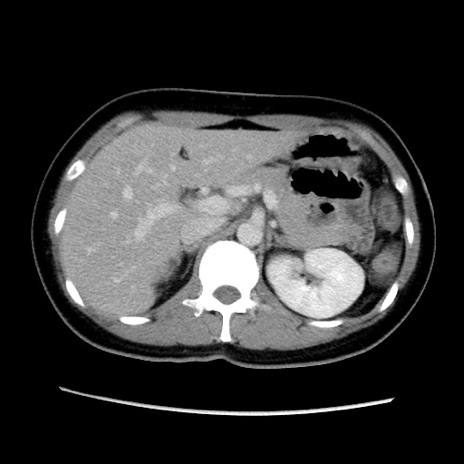

症例39(横断像)

【症例】40歳代女性

【主訴】上下腹部痛

【現病歴】2日目から下腹部痛あり。夜間は痛みで眠れなかった。昨日より上腹部痛と下痢が出現。臥位で痛みは軽快したため、休んでいた。本日になって臥位でも立位でも痛みが強くなってきたため救急要請。

【既往歴】子宮内膜症

【身体所見】部:平坦・軟、左上下腹部に圧痛あり、反跳痛あり。

【データ】WBC 21800、CRP 26.78